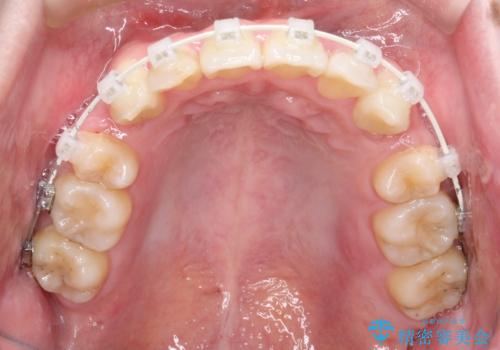

- 矯正装置

- 審美装置

ブリッジを装着している歯は動かすことができないので、矯正前に除去する必要があることがあります。

今回の場合も、ブリッジを除去して矯正後にセラミックブリッジを装着しました。